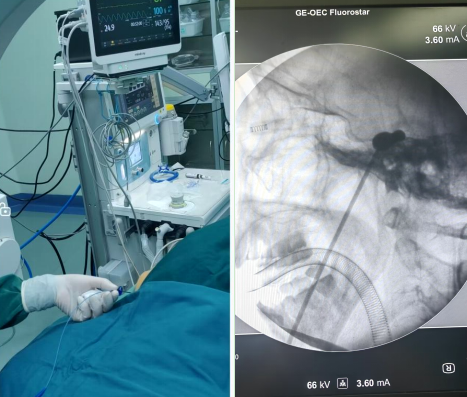

2024年12月21日,呼和浩特市第一医院疼痛科完成医院首例经皮三叉神经半月节球囊压迫术。

患者老年女性,右侧面部疼痛16年,加重8月。患者治疗经过较为复杂,曾行三叉神经神经阻滞治疗、三叉半月节射频热凝术、半月神经节伽马刀放射治疗等,效果均一般。来我院就诊后,疼痛科在首都医科大学宣武医院功能神经外科郭松教授的指导下,神经外科、骨脊柱科及麻醉科的支持下,完成经皮三叉神经半月节球囊压迫术。患者术后2天疼痛缓解80%,局部略有麻木,效果确切。

球囊压迫技术是近年来国内外推荐技术,它以短时间内给予麦氏囊内缓慢充盈的压力传递至半月节,利用痛觉神经细小易损、感觉神经元粗大耐压的特点,以获得不痛、远期不麻且不易复发的疗效,是值得推荐的一种治疗三叉神经痛的微创手术。